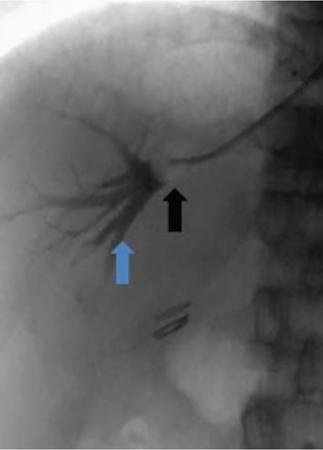

Amar Mukund, Shaleen Rana Portal hypertension (PH) is an inevitable complication of chronic liver disease. Chronic liver disease results in increased vascular resistance due to fibrosis and increased sinusoidal tone. Associated increase in portal flow is seen due to hyperdynamic circulation and expanded plasma volume which is a result of splanchnic vasodilatation and neoangiogenesis. Splanchnic vasodilatation further activates the vasoactive pathways secondary to systemic underfilling, resulting in ascites and renal derangement. As the portal pressure increases there is a transition from the subclinical to the clinical phase. Increasing portal pressure causes a gradient between the portal vein and inferior vena cava (IVC) known as the portal pressure gradient (PPG). The increasing gradient coupled with neoangiogenesis opens up portosystemic collaterals and formation of varices. The asymptomatic stage is called compensated cirrhosis (CC) or compensated advanced chronic liver disease. The patients with hepatic venous pressure gradient (HVPG) between 5 and 10 mm Hg are labelled as mild PH while those with HVPG >10 mm Hg are labelled as clinically significant portal hypertension (CSPH). The onset of CSPH is associated with various complications of PH. The causes of PH have been classified into (1) Prehepatic (portal, splenic or mesenteric vein thrombosis), (2) Intrahepatic (diseases like viral/alcoholic hepatitis) and (3) Posthepatic (Budd–Chiari syndrome). Complications of PH like ascites, encephalopathy and variceal bleeding increase the morbidity and mortality in patients with chronic liver disease and are directly proportional to the increasing portal pressure. Early recognition and diagnosis of PH and its types can help to prevent development of complications in an asymptomatic patient and to treat the complications in a symptomatic patient. Subclinical PH usually has no positive signs on examination. Presence of splenomegaly, abdominal wall collaterals, ascites and spider naevi suggest advanced disease. Various parameters like albumin, international normalized ratio (INR), platelets and liver function tests have been used in various combinations (Fibroindex, AST – platelet ratio index and Fibrosis – 4) and attempts have been made to correlate with progression of fibrosis and PH with reasonable degree of success. Ultrasound and contrast-enhanced CT/MRI are good in depicting the complications of chronic liver disease however none of the modalities measures the HVPG and do not correlate well with HVPG. TE can be used as a tool for assessing liver stiffness in patients with chronic liver disease. Baveno VI consensus workshop recommends that TE values >15 kPa suggests CC and screening endoscopy can be avoided in patients with liver stiffness <20 kPa and platelet count >1,50,000 as these patients have very lower risk of varices. The above-mentioned noninvasive modalities lack the sensitivity and specificity of HVPG and none of these modalities directly measure the HVPG. HVPG is an invasive technique which helps in determining portal pressure using a catheter placed in one of the hepatic veins. When a catheter is wedged in the hepatic vein the proximal column of blood reflects the pressure within the hepatic sinusoids. In cirrhosis, there is loss of normal connections within the sinusoids and the wedged hepatic venous pressure (WHVP) represents the portal pressure. Hepatic vein pressure gradient (HVPG) is calculated by subtracting free hepatic venous pressure (FHVP) from the WHVP. HVPG measurement is currently considered the gold standard for measurement of portal venous pressure in chronic liver disease. HVPG is helpful in diagnosing and measuring the severity of PH. HVPG predicts the severity of cirrhosis, clinical course in chronic hepatitis B and C infections and the development of complications. It is a surrogate clinical marker and has been used for prognostication and treatment response. HVPG >10 mm Hg is associated with formation of oesophagal varices while HVPG >12 mm Hg is associated with increased risk of variceal bleeding and ascites. A baseline HVPG of ≥16 is associated with increased risk of death irrespective of presence or absence of varices with no bleeding. Patients with HVPG ≥20 mm Hg presenting with variceal bleeding are more likely to have early rebleeding or inability to control bleeding than patients with HVPG <20 mm Hg. There is a higher transfusion requirement, longer intensive care unit stay and increased mortality in patients with HVPG ≥20 mm Hg. Decrease in HVPG to ≤12 mm Hg with pharmacotherapy or improving liver functions prevents variceal bleeding and reduces the size of existing varices. Similarly, ≥20% reduction in baseline HVPG reduces the risk of bleeding, variceal rebleed, ascites and mortality. Serial measurements of HVPG have been used for assessment of response to Hepatitis C treatment and effect of pharmacological therapy in lowering portal pressure. Several studies showed that there was significant reduction in HVPG posttreatment for hepatitis C infections. Preoperative use of HVPG in patients undergoing hepatectomy has been found to predict post hepatectomy decompensation and is more likely to occur in patients with CSPH (HVPG >10 mm Hg). HVPG also predicts recurrence or onset of hepatitis C cirrhosis in transplant patients and HVPG >6 mm Hg in these patients is associated with disease progression. HVPG measurement via hepatic vein catheterization is simple, safe and reproducible technique with immense clinical benefit. Hepatic vein catheterization is done under conscious sedation in a daycare setting with continuous monitoring of the vitals during the procedure. The patient should be fasting for minimum 6 hours. Venous access (Internal jugular, femoral or ante cubital vein) is secured under local anaesthesia. A balloon-tipped catheter is advanced into the right hepatic vein through the internal jugular vein (IJV) or IVC over a guidewire. Contrast is injected through the balloon catheter to confirm the position of the catheter and the diameter of the vein. FHVP is measured by letting the catheter tip float freely in the hepatic vein for at least 15 seconds within 5 cm of the hepatic vein ostium. WHPV is measured by inflating the balloon so that it is well opposed to the venous walls and the pressure tracing is stable for a minute (Fig. 9.26.1). After measuring the pressure adequate occlusion of the vein is confirmed by injecting 3–5 mL contrast slowly which should result in a wedge sinusoidogram, no reflux via collateral veins, absence of venous waveform and no blood on applying suction through the catheter. In the event of inadequate occlusion, the pressure is measured again and occlusion is verified again. Three readings are taken if the variation is ≤1 mm Hg and a mean of the values is considered. Permanent recording of the tracing using a multichannel recorder is done. The HVPG is calculated by subtracting FHVP from the WHVP. The advantage of measuring the gradient is that it is unaffected by changes in abdominal pressure, ascites or the hydration status of the patient. Venous pressure should also be measured in the IVC and the right atrium (RA). The IVC pressure should be measured at the level of the hepatic vein ostia because the pressure may be higher inferiorly due to compression of the IVC by hepatic parenchymal hypertrophy. The gradient between the hepatic veins and the RA should not be more than 2 mm Hg. If the gradient is >2 mm Hg then one must suspect a narrowing or a web in the hepatic vein or the IVC. Using RA pressures for HVPG measurement has the advantages of easy reproducibility and that it measures the actual portosystemic gradient. WHVP should be separately mentioned as it represents the pressure of blood in the varices and hence risk of variceal rupture. Patients coughing, movement or talking should also be recorded as it may cause artefacts while recording a trace. After successfully measuring the pressures the catheter and the sheath is removed and manual compression of the puncture site is done till the oozing stops followed by immobilization of the part for at least 4 hours. Some points to be kept in mind while measuring HVPG. HVPG measurement is a safe procedure with no major complication or mortality. Puncture site leakage and hematoma of the access vessel are the common complications. Rare complications are vasovagal syncope and arteriovenous fistula formation. Most of the complications can be avoided by using ultrasound for puncture of the access vessels and adequate postprocedural compression. Self-limiting supraventricular arrhythmias may be seen when the wire or the catheter traverses the RA. TJLB was introduced to reduce the complications associated with percutaneous liver biopsy (PLB) in patients with ascites, coagulopathy or in patients whose percutaneous biopsy had failed. Transjugular biopsy is now an acceptable and established technique for obtaining biopsy from the liver with no incidence of major complications. TJLB is done as a daycare procedure. Patient has to be fasting for 6 hours and an informed consent should be taken. The patient is shifted to a procedure room/cath-lab and the right neck is cleaned and draped. Continuous monitoring of the vitals is done throughout the procedure. Under local anaesthesia right IJV is accessed and a 10 F vascular sheath is introduced. Through the sheath, right hepatic vein is accessed using a 5F catheter and J tip floppy guidewire (Terumo, Japan). A contrast run is taken to confirm the position of the catheter in the right hepatic vein. The floppy guidewire is exchanged with a 0.035-inch stiff guidewire over which a curved stiff TJLB cannula is advanced. The stiff TJLB cannula is wedged against the wall of the hepatic vein. Wedging prevents the needle from slipping while taking a tissue core. This is followed by introduction of the semiautomatic coaxial biopsy gun (Fig. 9.26.2). Two to three cores are taken. The needle should be directed anteriorly when taking a biopsy from the right hepatic vein and laterally while taking biopsy from the middle hepatic vein. A contrast run is taken postprocedure. Postprocedure the neck access site is compressed manually and patient is monitored for 4–6 hours. If patient complains of severe pain not relieved by analgesics or if there is any tachycardia/fall in blood pressure, ultrasound should be done to rule out hemoperitoneum. Following important steps not to be overlooked.